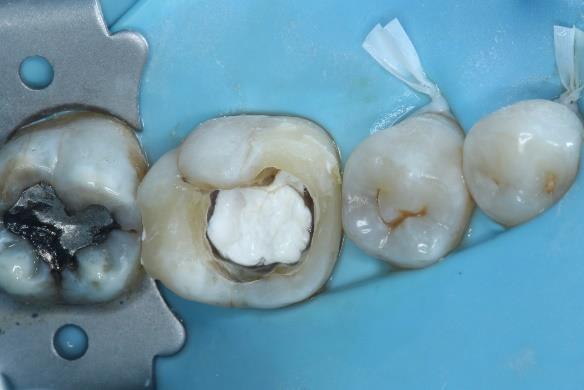

Dr. Dhiraj Arora: A Simple Sequence for Successful Root Canal Treatment Outcomes (EN)